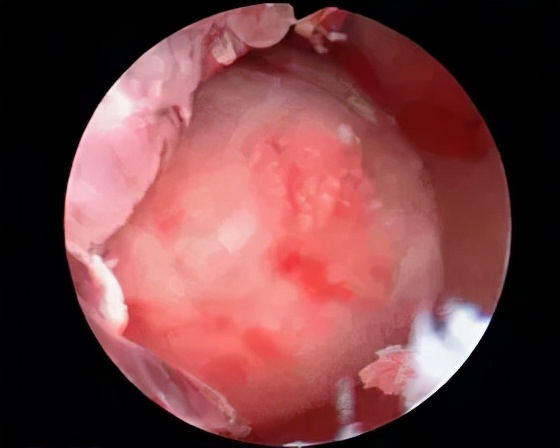

1.正常宫腔

2.黏膜下子宫肌瘤

3.子宫内膜息肉

4.宫腔粘连

6.子宫腺肌症

7.子宫内膜癌